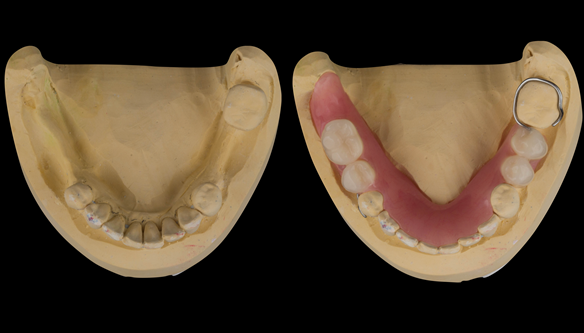

This newsletter describes in step by step detail Angela's transition through immediate partial dentures to crown supported definitive metal based dentures.

The clinical situation and treatment process is shown in detail below with photographs. I (Finlay Sutton) provided the clinical work and Rowan Garstang provided the technical work.